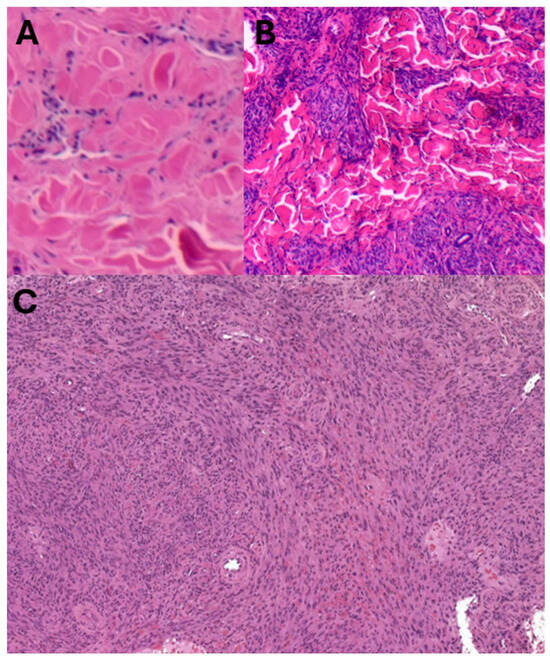

Figure 2.

Traditional KS morphology: Sparsely cellular patch KS (A), increased spindle cells in plaque KS (B), and densely cellular spindle cell proliferation in nodular KS (C) [haematoxylin and eosin stain].